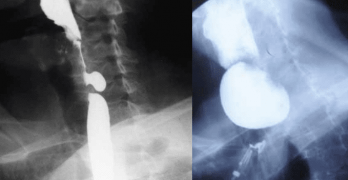

La disfagia orofaríngea (DO) o dificultad en la deglución es una patología importante en muchos pacientes con enfermedades neurológicas y en personas de edad avanzada. La DO tiene un código específico (787.2, R13) en las últimas versiones de la Clasificación Internacional de Enfermedades (CIE-9 y CIE-10), publicadas por la Organización Mundial de la Salud.